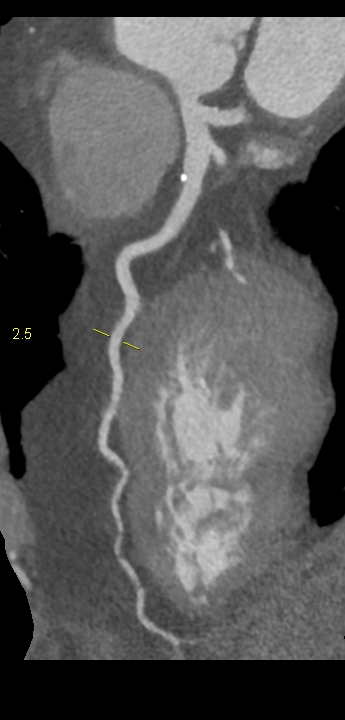

Figururile 1-9: reconstrucție în axul lung al vasului pentru arterele coronare cu evidențierea unui calibru global crescut la nivelul acestora și cu încărcătură ușoară-moderată de placă în principal calcificată

Discuţie caz nr 132: Examinările coroCT se efectuează în principal pentru aprecierea încărcăturii de placă precum și pentru evidențierea reducerilor de lumen ce necesită tratament. Această examinare a evidențiat creștere globală a calibrului arterelor coronare și o încărcătură ușoară-moderată cu placă în principal calcificată, fără a se evidenția arii de stenoză.

DE LUAT ACASĂ!!! Ectazia coronariană este o afecțiune rară caracterizată prin dilatarea anormală (diametrul vasului este de 1.5 ori mai mare) a arterelor coronare, care poate duce la afectarea fluxului sanguin și la un risc crescut de ischemie. Etiologia nu este cunoscută iar afecțiunea poate fi asociată cu ateroscleroză sau factori congenitali și reprezintă o provocare atât în diagnostic, cât și în tratament. Simptomele se suprapun adesea cu cele ale altor boli coronariene, ceea ce face ca identificarea timpurie să fie crucială. Opțiunile de tratament variază de la tratamentul medical cu terapie antiplachetară sau anticoagulantă până la proceduri intervenționale, cum ar fi angioplastia sau intervenția chirurgicală, în funcție de severitatea și riscul de complicații. Tratamentul pe termen lung se concentrează pe prevenirea evenimentelor ischemice și pe abordarea cauzelor care stau la baza acestora.